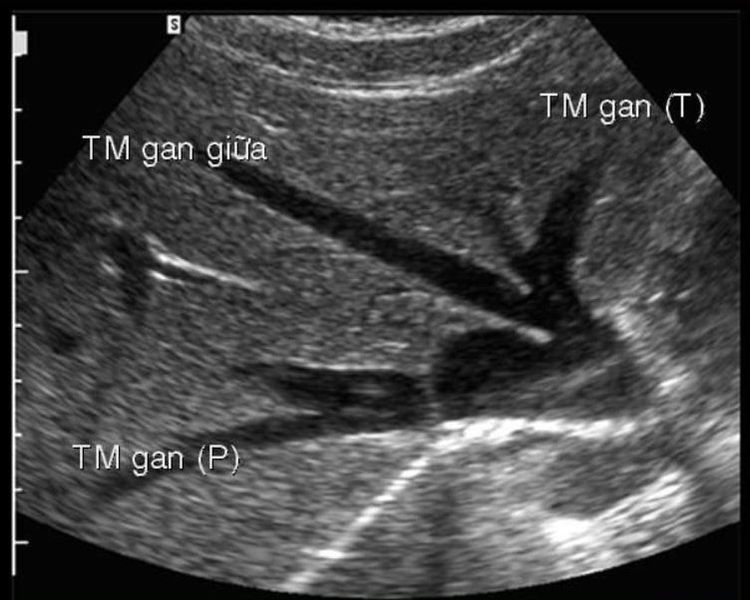

Hình ảnh siêu âm gan.